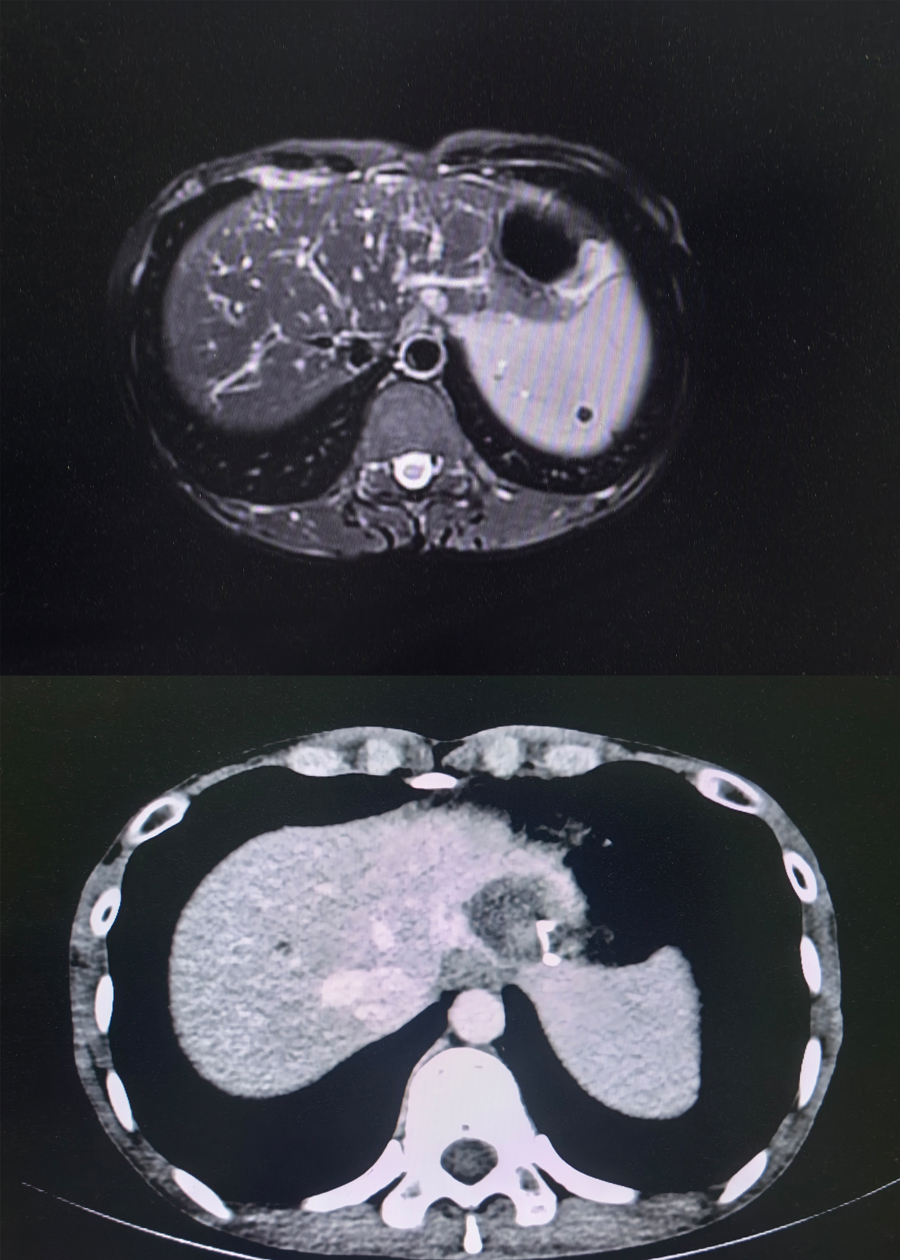

术前术后影像良友对比

术后即时造影阐明,患者肿瘤组织被完好消融,毗邻艰苦器官结构毫发无损,术后增强CT扫描及三维重建检查进一步证实,肿瘤已终了完好消融,手术获取圆满见效。